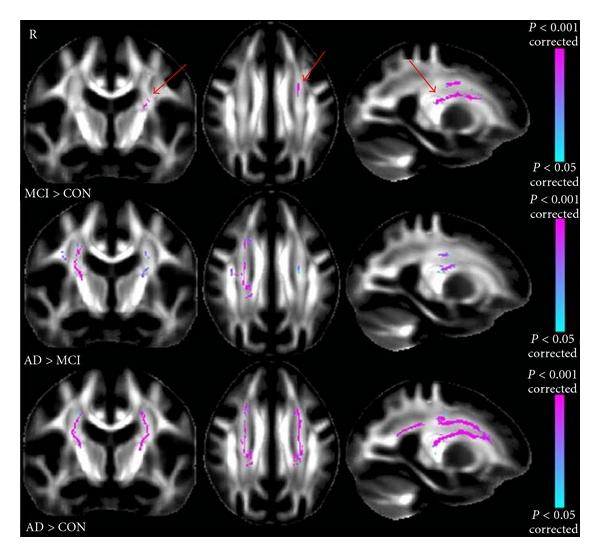

DTI measures in crossing-fibre areas: increased diffusion anisotropy reveals early white matter alteration in MCI and mild Alzheimer's disease.

交叉纤维区域的 DTI 测量:扩散各向异性增加揭示了 MCI 和轻度阿尔茨海默病的早期白质改变。

Neuroimage. 2011 Apr 1;55(3):880-90. doi: 10.1016/j.neuroimage.2010.12.008. Epub 2010 Dec 21.